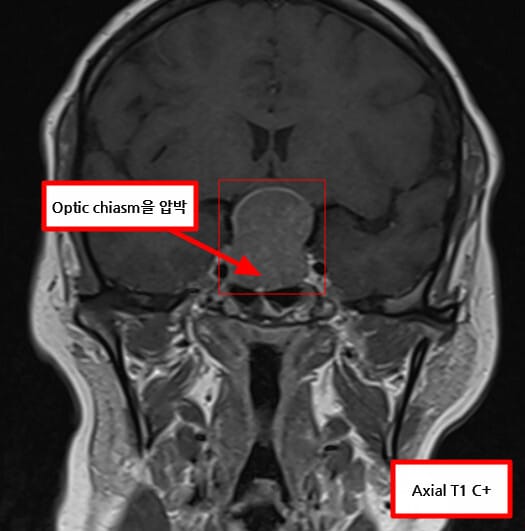

| 🟨 시야장애 (양측 반맹) |

| 시신경 교차부(Optic Chaism)를 압박하여 외측 시야가 손상됩니다. |

| ✅ 시신경 교차 압박 가능성 |

| 상방으로 확장된 종양이 시신경을 눌러 시야장애를 유발합니다. |